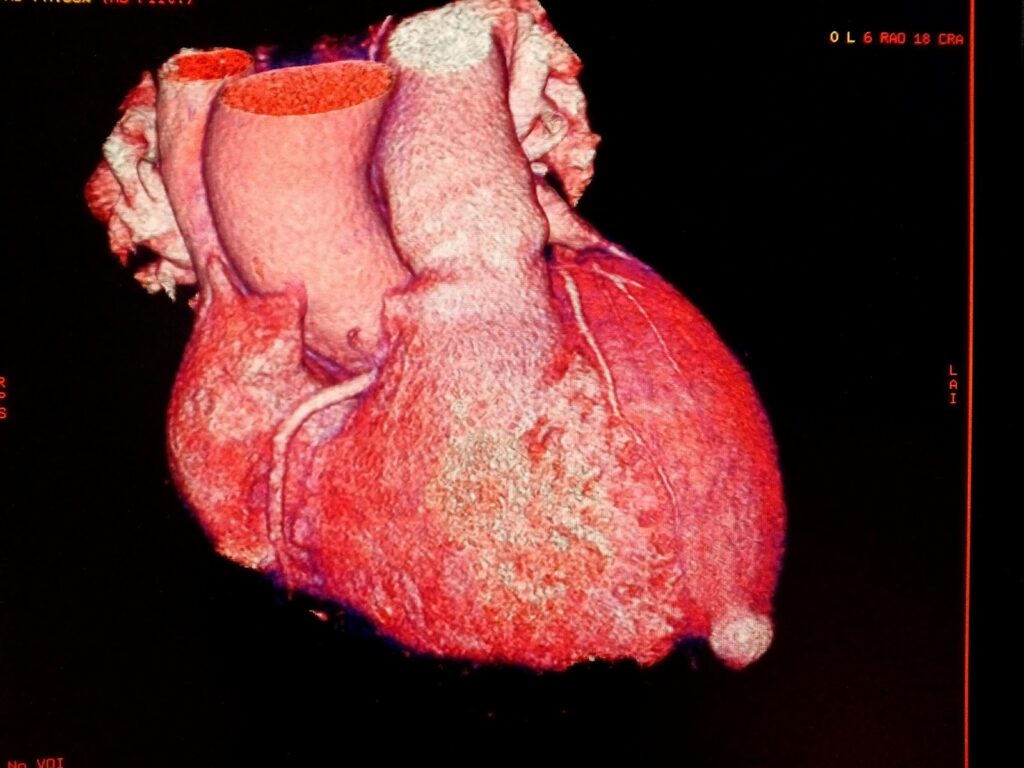

Los aneurismas del ventrículo izquierdo se identifican mediante la persistencia de una elevación del segmento ST en el electrocardiograma, que se observa más allá de un período de cuatro a ocho semanas después del infarto. Este hallazgo es indicativo de un proceso patológico en curso y puede sugerir la formación de un aneurisma. Además, en la evaluación por imagen, se puede observar un cuello ancho que conecta el aneurisma con el ventrículo izquierdo. Esta conexión puede ser visualizada con técnicas como la ecocardiografía, la cintigrafía y la angiografía con contraste, las cuales proporcionan información detallada sobre la estructura y la función del corazón.

Un aneurisma del ventrículo izquierdo se define como una área de cicatriz miocárdica que presenta una forma bien delimitada y que, durante la sístole, experimenta un abultamiento inusual, lo que resulta en un comportamiento paradójico del tejido afectado. Este fenómeno es particularmente relevante en el contexto de pacientes que han sobrevivido a un infarto agudo, ya que se estima que entre el diez y el veinte por ciento de estos pacientes desarrollan un aneurisma tras el evento isquémico. Este tipo de aneurisma es más común en aquellos que han sufrido infartos por elevación del segmento ST en la pared anterior del corazón, donde el daño al miocardio es más extenso y, por lo tanto, más propenso a la formación de cicatrices.